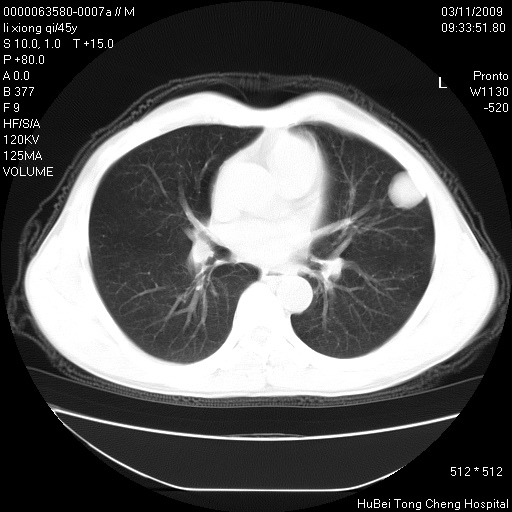

患者 男,45岁。胸痛,咳嗽伴痰中带血1月余。

临床诊断:肺结核?

胸部ct轴位平扫(层厚10mm,螺距1.5,重建间隔10mm),图像如下:

考虑肝癌肺转移

考虑肝癌肺转移。

肝癌肺转移